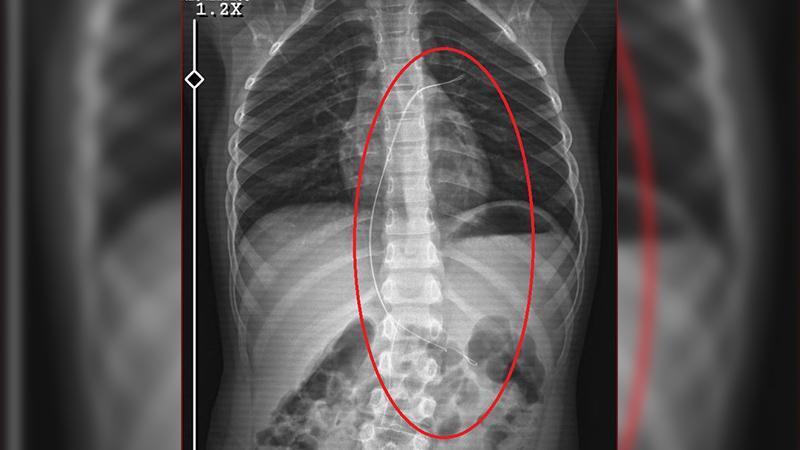

Şırnak’ta yaşayan Semra (37) ve Mehmet Ötün (40) çiftinin oğulları Aram Devran Ötün, mayıs ayında piknikteyken salatalık parçası yuttuktan sonra öksürük ve kusma şikayetleri görülünce Şırnak Devlet Hastanesi’ne götürüldü. Burada çekilen röntgen ve MR’da Aram’ın vücudunda kateter unutulduğu görüldü. Diyarbakır’daki Gazi Yaşargil Eğitim ve Araştırma Hastanesi Kadın Doğum ve Çocuk Ek Binası’na sevk edilen Aram, 5,5 saat süren riskli bir ameliyata alınarak 18 santimetre uzunluğundaki kateter çıkarıldı. Ameliyat sonrası yapılan incelemelerde kateterin kalp kapakçığına ve ciğerlerine zarar verdiği belirlendi.

Ailenin avukatı Ahmet Yalçın, hastane hakkında hem şikayetçi olduklarını hem de dava açtıklarını belirterek, “Müvekkilim Aram Devran Ötün, 2022 Eylül ayında Dicle Üniversitesi Hastanesi’nde Stevens- Johnson hastalığı nedeniyle tedavi gördü. Tedavi sırasında kendisine kateter takıldı. 18 santimetre uzunluğundadır. Bunu takarken büyük bir ihmalkarlık yapılarak vücudunda unutuldu. Mayıs ayında müvekkilim çok öksürdüğü için Şırnak Devlet Hastanesi’ne kaldırıldı. Burada yapılan tetkiklerde kateterin unutulduğu tespit edildi. Daha sonra Diyarbakır Gazi Yaşargil Kadın ve Çocuk Hastalıkları Hastanesi’ne götürüldü. Çok riskli bir ameliyata alındı ve kateter çıkarıldı. Bu kateterin vücutta yol aldığı tespit edildi. İlk giriş yeri ve çıkarıldığı yer arasında çok fark var ve kalp kapakçığı ile ciğerlerine zarar verdiği tespit edildi. Müvekkillerimin hem maddi hem de manevi zararlarını karşılamak adına Dicle Üniversitesi’ne biz başvuruda bulunduk. 30 günlük cevap süresi içerisinde bize geri dönüş yapılmadı. Biz de maddi ve manevi zararların tazminat için Diyarbakır İdare Mahkemesi’ne davamızı açtık ve sorumlulardan şikayetçi olduk” dedi.

Oğlunun piknikte salatalık parçası yuttuktan sonra sürekli öksürmeye ve kusmaya başladığını söyleyen Semra Ötün, “Çocuğum 3 yıl önce Steven Johnson sendromu hastalığına yakalandı. Milyonda bir görülen antibiyotikten kaynaklı bir hastalık. Doktorlar öyle söyledi. Bizi acilen Diyarbakır Dicle Üniversitesi Çocuk Hastanesi bölümüne sevk ettiler. 1 ay yoğun bakım sürecimiz oldu. 28 gün yoğun bakımda, 3 günde serviste kaldı. Damar yolundan, kasıktan serum taktılar. Kateter denilen tel çocuğun vücudunda bırakılıyor. Biz taburcu olduğumuzda fark edilmiyor. 3 yılın sonunda biz bunu fark ettik. Pikniğe gittik. Oğlum salatalık parçası yuttu ve salatalık parçasından sonra akşama kadar öksürdü. Hiçbir şekilde durmadı. Kusuyordu. Ben şüphelenmeye başladım. Çocuğum normal değildi. Sonra eşime danıştım. Akşam 21.00 civarında acile götürdük. Röntgeni ve MR’ı çekildi. Tuhaf bir şey olduğunu anladık. Doktor röntgeni gösterdi. Tel kalmıştı. Çok kötü bir şekilde. Acil doktoru film çektikten sonra bize bir tel parçasını gösterdi. Bizi bekletmeden Diyarbakır’a sevkimizi verdiler. Diyarbakır Gazi Yaşargil Eğitim ve Araştırma Hastanesi Kadın Doğum ve Çocuk Ek Binası’na gittik. Çocuğun kasıklarından anjiyo yolu ile teli çıkaracaklarını ama riskli bir ameliyat olduğunu söylediler. O süreçte çocuk gerçekten sürekli yoruluyordu. İkide bir oturuyordu. ‘Anne çok yoruldum, karnım ağrıyor’ diyordu. Ben ağrı kesiciler ile geçiştirmeye çalışıyordum. Bu telin 3 yıl boyunca çocuğumda kaldığını öğrendim. Ailece yıkıldık” diye konuştu.